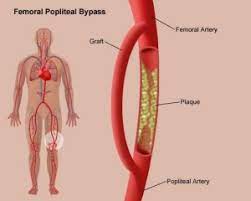

Overview

Package includes:

Days in hospital : 7 to 8 Days (For patient and one attendant)

Days in hotel : 14 Days (For patient and one attendant)

Room type in hospital : Shared

Room type in hotel : Private

Hotel category: Standard

Value added benefits of the Femoro Popliteal Bypass:

Ø Doctor consultation charges

Ø Lab tests and diagnostic charges

Ø Room charges inside hospital during the procedure

Ø Surgeon Fee

Ø Nursing charges

Ø Hospital surgery suite charges

Ø Anesthesia charges

Ø Routine medicines and routine consumables (bandages, dressings etc.)

Ø Food and Beverages inside hospital stay for patient and one attendant.

Extra benefits:

ü Interpreter

ü Visa assistance

Ø Site tourism of the city

Ø Follow up with the doctor

Ø Airport pick up and drop

Ø Free online consultation with the doctor

Ø Priority appointments with the doctor

Ø Room upgrade from sharing to private